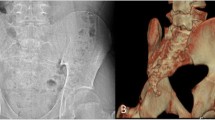

A quasi-automatic 3D reconstruction of the spine was performed in three steps, which will be detailed below: The operator first selected a few anatomical landmarks on the frontal and lateral radiographs (Fig. 1a), and then, an automatic algorithm provided an initial solution of 3D reconstruction, on which the operator could perform fast manual adjustment of some key vertebrae (the apex, junctions and the adjacent to the junctions, Fig. 1b) which were projected over the original radiography (Fig. 2).

a Manual initialization of the 3D reconstruction. The sacral plate, acetabula and the spinal midline from the odontoid apophysis of C2 vertebra to L5 lower endplate were selected in both views. The upper endplate of C7 and lower endplate of T12 were selected in the lateral view, while the main scoliotic curve was selected in the frontal view. b 3D reconstruction of the seven key vertebrae that were manually adjusted: the apex, the junctional vertebrae and the adjacent to the junctional vertebrae

Position of the vertebral model for apical vertebra (L2) before (a) and after manual adjustment. In b, the contour does not perfectly match the vertebra because only fast rigid transformations (translation and axial rotation) were required to compute the severity index. In this example, the vertebra was displaced by 3 mm (corresponding to 16 pixels) and it was axially rotated by less than 1°

More in detail, the following landmarks were digitized in both views (Fig. 1): the sacral plate, left and right acetabula and the spinal midline through the center of all vertebral bodies, from the odontoid apophysis of C2 to L5 lower endplate. The upper endplate of C7 and lower endplate of T12 were also selected in the lateral view, while the two endplates delimiting the main scoliotic curve were selected in the frontal view. The junctional levels of the main curve were defined to obtain the maximization of Cobb angle, and they were often characterized by a local discontinuity of vertebral axial rotation (i.e., a sudden change of vertebral axial orientation).

The initial solution was automatically calculated through statistical inference [20, 21] and image analysis [22, 23]. The 3D reconstructed vertebrae thus obtained were retro-projected (Fig. 2) on the frontal radiography. The operator was only required to adjust horizontal and vertical position and axial rotation of seven key vertebrae: the curve apex, two junctional vertebrae and the adjacent to the junctional vertebrae. The aim of this step was to better fit the projection of the 3D model to the frontal radiography; the sagittal radiography was not used at this stage since the initial solution was sufficiently accurate in this plane.

The initial manual identification of the spinal curve and specific endplates lasted 2.5 min in average, while the final manual adjustment of seven key vertebrae lasted less than 1 min. Figure 2 shows an example of rigid manual adjustment.

Overall, the apexes were displaced by 0.1 ± 0.2 mm (max 4.2 mm) and rotated by 0.1 ± 0.1° (max 1.8°).